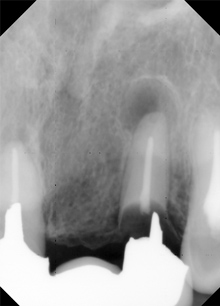

![]() |

歯ぐきや骨の下までむし歯が進み歯の根が残っている状態です。 |

|

歯の根の中にやや太いワイヤーを入れ高品質ゴムにて牽引します。 |

健康な歯根の一部が歯ぐきの上に挺出され治療が可能な状態となります。 |

以前に治療されていた差し歯が取れてきました。 |

歯の根の中にやや太いフック付のワイヤーをいれて |

両脇の歯を抵抗源(アンカー)にして |

硬く、健康な歯ぐきが増え、歯を取り巻く骨も多くなります。 |

歯の根を利用して金属で補強します。 |

歯ぐきも健康を取り戻し、審美修復ができています。 |

お口の中からでは一見はずれていて、悪くなっているかわからないブリッジタイプの修復物です。 |

ブリッジの悪い部分を取ってむし歯をこの時点でできるだけとって根の治療からはじめます。 |

やや太いフック付のワイヤーを屈曲して歯の根の中にいれ、隣り合っている歯を

支えにするために(アンカー)

補助装置(横のワイヤー)をつけます。 |

横のワイヤーとフックが着くまで挺出・牽引ができました。 根端病巣も治りつつあります。 |